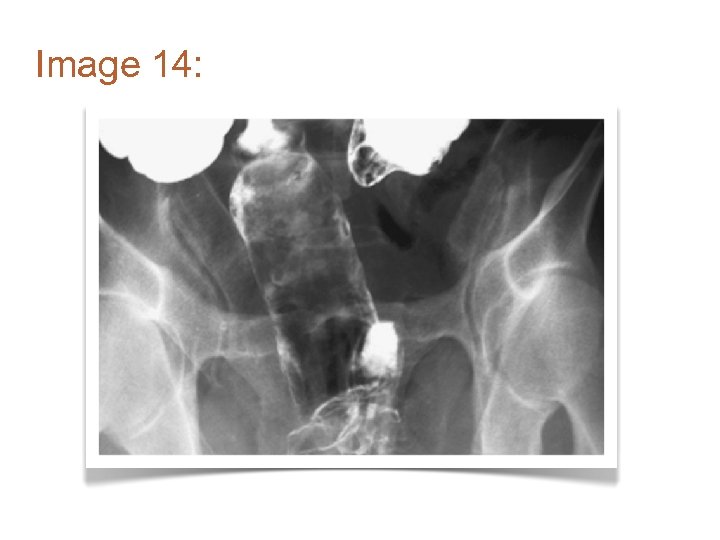

Image 14: